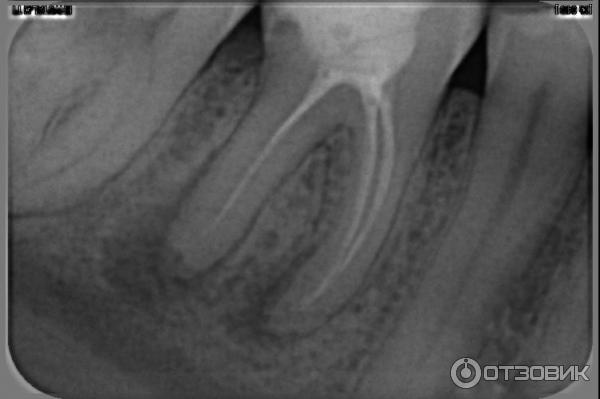

Не до конца запломбировали канал